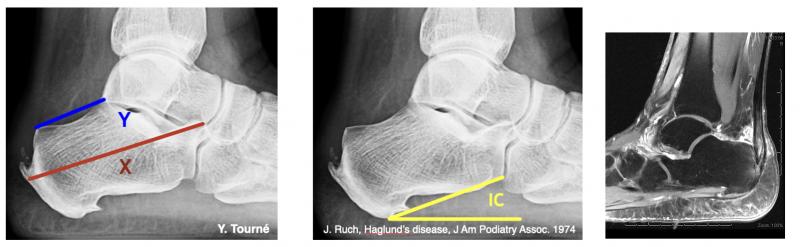

4. Tendinopathies d’insertion – Maladie de Haglund

Physiopathologie : conflit entre le contrefort de chaussure et le coin postéro-supérieur du calcanéus, parfois associé à une dégénérescence d’insertion.

Clinique : douleur postérieure haute, tuméfaction, gêne au chaussage.

Imagerie : radiographie de profil (angle calcanéen > 20°, rapport X/Y < 2,5), IRM (enthésophyte, bursite, désinsertion partielle).

Prise en charge : traitement médical (semelles, kiné, adaptation chaussage). Si échec : chirurgie selon la morphologie calcanéenne : résection isolée, ostéotomie de Zadek ou désinsertion-réinsertion type SpeedBridge®.